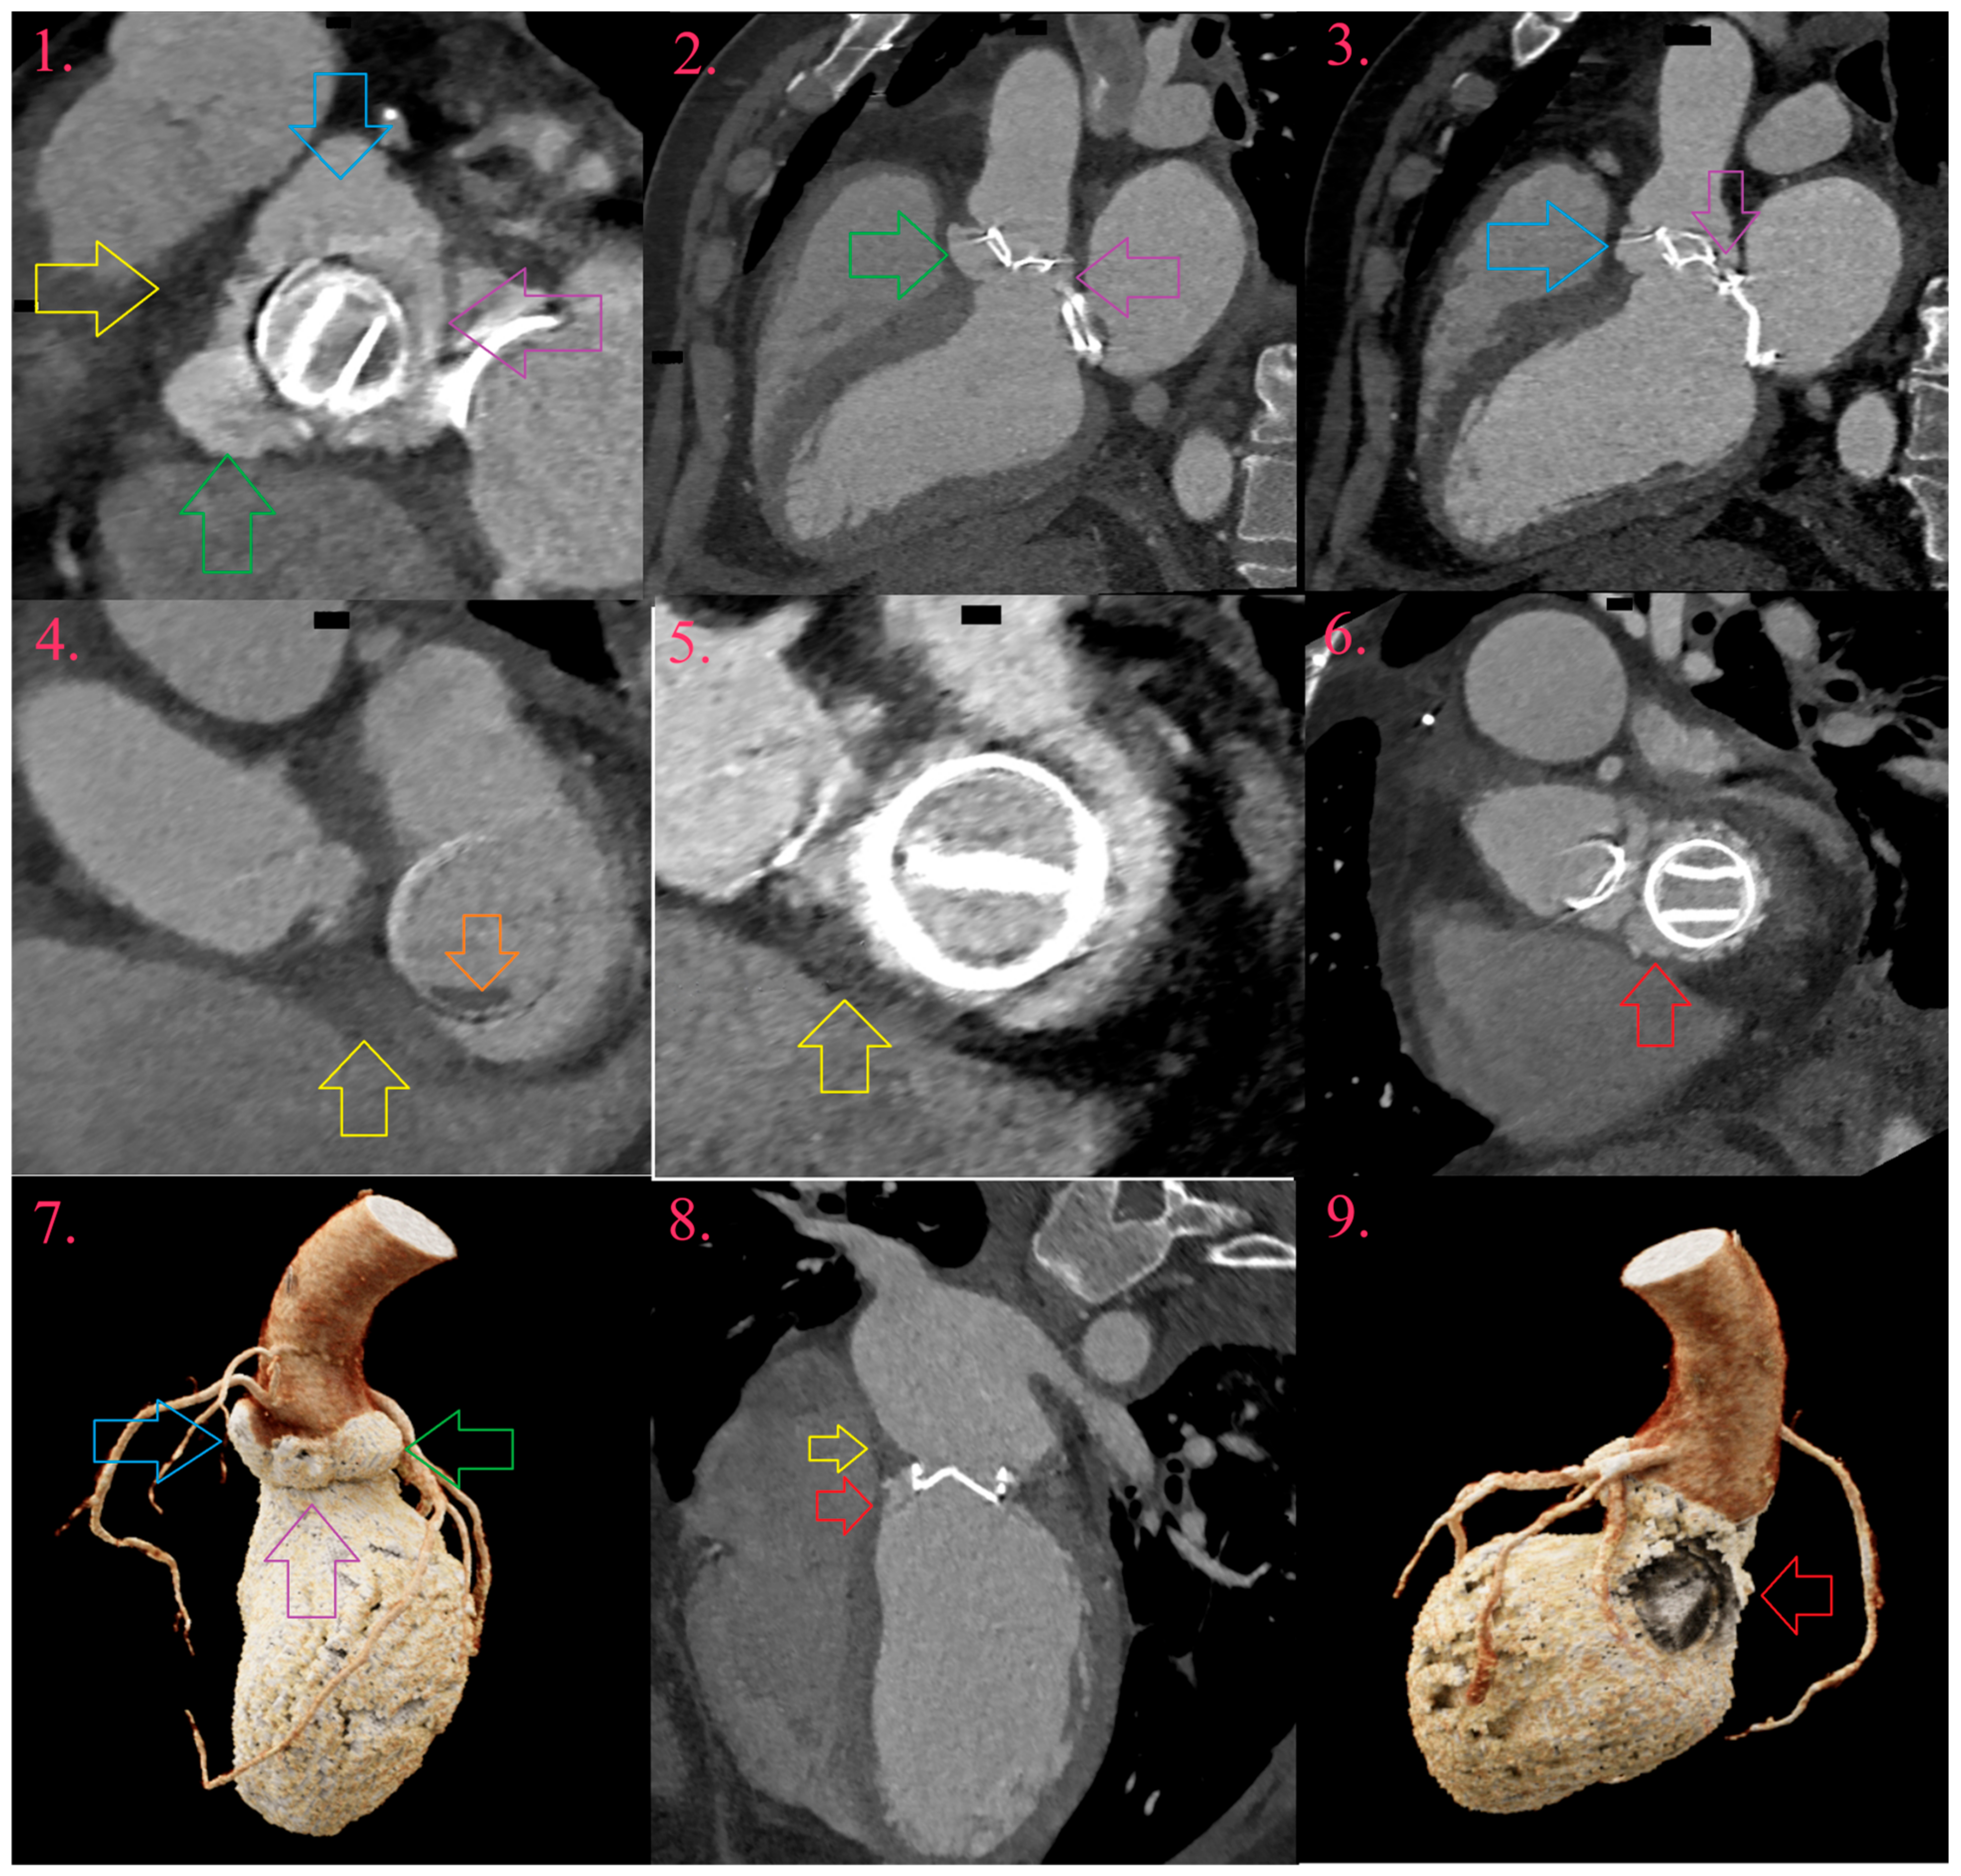

Figure 5.

Multivalvular left-sided PVE. Around artificial aortic valve there is pseudoaneurysm abutting its entire circumference (Image 1, Image 2, and Image 7, green arrow), with development of two fistula between aorta and left ventricle, through left coronary sinus (Image 1, Image 3 and Image 7, blue arrow) and aortomitral fibrosis (Image 1, Image 2, Image 3 and Image 7, purple arrow). There is abscess towards right ventricle outflow tract (Image 1, yellow arrow) and right fibrous trigonum (Image 4, Image 5, and Image 8, yellow arrow), with development of pseudoaneurysm around artificial mitral valve in left ventricle outflow tract (Image 6, Image 8, and Image 9, red arrow). At the tip of the artificial mitral valve, there is vegetation toward left atrium (Image 4, orange arrow).

Gahide et al. reported sensitivity and specificity of CCT in detection of pseudoaneurysms as 100% and 87.5%, in aortic IE in 19 patients [46]. Sifaoui et al., in 68 patients, reported sensitivity and specificity of CCT in pseudoaneurysm detection as 100% and 96.8% in comparison to TEE 72.7% and 89.1% [54]. The majority of studies report mutual sensitivity and specificity of CCT in detection of abscesses and pseudoaneurysms in a range 60–100% and 78.4–100% vs. TEE 40–92.3% and 89–100% [45,48,50,51]. CCT depicts pseudoaneurysms independent of their localization, accurately assesses depth and size of its cavities and the percentage of the circumference of the annulus involved, information which is relevant to the surgeon [31].